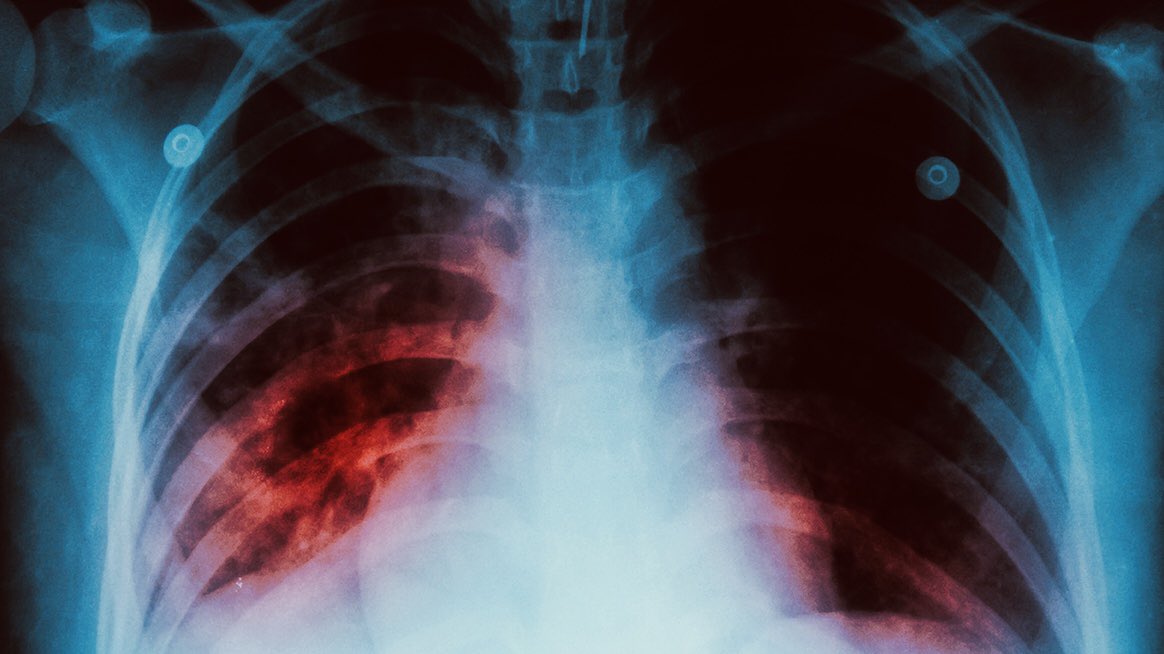

"mycobacterium tuberculosis" هي البكتيريا المسببة للسل، وتنتقل عبر جزيئاتٍ في الهواء فتدخل لمجرى التنفس وتصيب الرئتين. في كثيرٍ من الأحيان يكون الجهاز المناعي قوي فيتغلب على هذه البكتيريا ولكن في حالات مرضى السكر، نقص المناعة، الحمل، وغيرها لا يستجيب بالشكل المناسب حتى يقضي عليها

فإذا استطاعت البكتيريا التغلب على الجهاز المناعي، تكاثرت داخل الخلايا المناعية وأفرزت أنزيمات تتسبب في القضاء على خلايا الرئة وهذا ما يسبب الآلام والسعال الدموي عند مرضى السل 🩸 التلف الحاصل في الرئتين يسبب نقص حاد في الأكسجين عند المريض وهذا بدوره يسبب تغيير في هرمونات الجسم